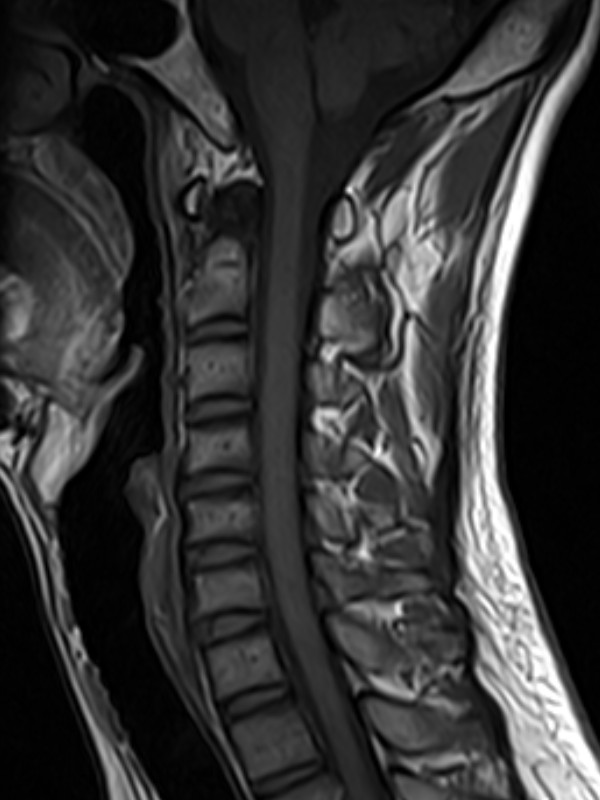

颈椎-T1

1524110739364692.jpg